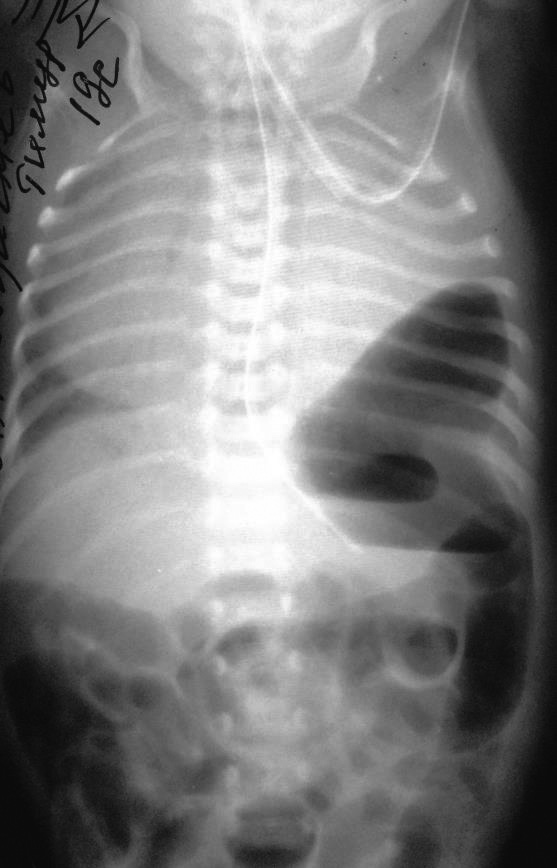

Попытки перевода на спонтанное дыхание были безуспешны, на рентгенограмме легких оставалась локальная зона просветления в проекции нижней доли правого легкого (рис. 4), что при наличии типичного положения печени, желудка, а также проведенного рентгенологического исследования с пассажем контраста, исключившим его наличие в данной тени (рис. 5), было расценено как остаточный локализованный пневмоторакс.

Рис. 4. Рентгенограмма органов грудной клетки. Локальная зона просветления в проекции нижней доли правого легкого.

Рис. 5. Рентгеноконтрастное исследование с пассажем контраста для исключения правосторонней диафрагмальной грыжи. Снимки на 10 мин, 30 мин, 1 ч. Контрастирования тени правой половины грудной клетки нет.